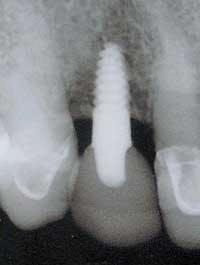

Figure 20 - Postop X-ray of immediate implant-abutment-crown. Immediate X-ray shows implant placement centered between the adjacent teeth.